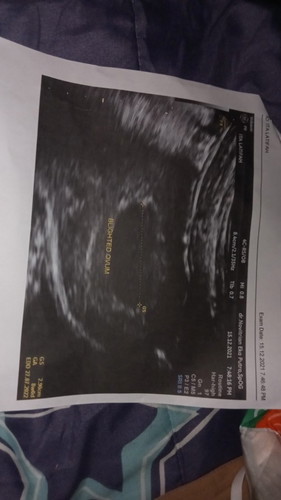

usia kehamilan 7 minggu 3 hari baru ada kantung janin saja

usia kehamilan 7 minggu 3 hari sesuai hpht tapi pas USG baru ada kantung janinnya saja itu bagaimana dok? saya langsung dikatakan hamil kosong dan suruh kuret tanpa disuruh balik lg untuk memeriksa kandungan minggu selanjutnya.. sudah satu minggu ini saya memang mengalami flek dan sering merasa pusing apa yang sebaiknya saya lakukan?Dan bahkan saya tidak dikasih obat apapun sama sekali... #bantusharing